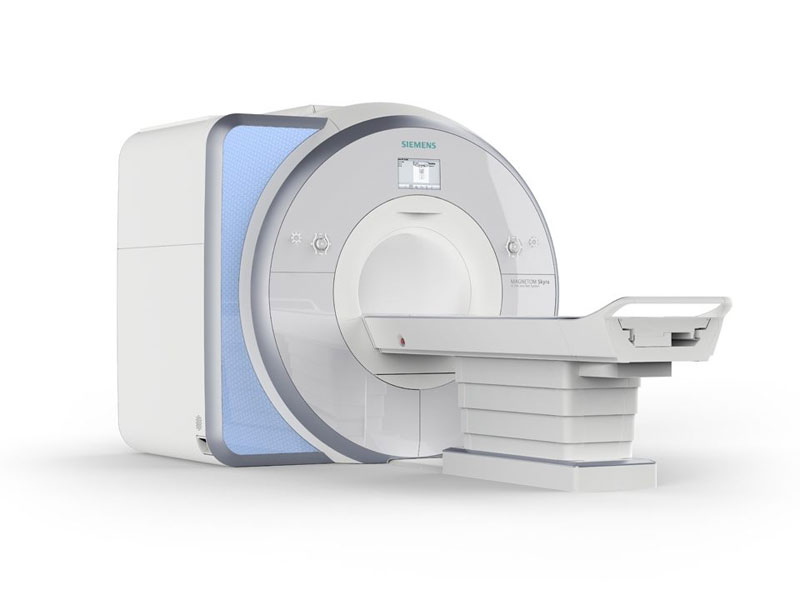

В рамках федерального проекта «Борьба с онкологическими заболеваниями» в Пироговском Центре установлен новый томограф для диагностики онкозаболеваний.